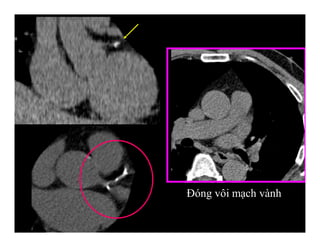

Đóng vôi mạch vành

-Đánh giá ‘Điểm Ca’

[Calcium score] là

phương tiện mới nhất

trong phát hiện và đánh

giá mảng xơ vữa động

mạch vành

-Có hướng xử trí thích

hợp: ăn uống, cách sống,

dùng thuốc, xét nghiệm

khác.

ĐIỂM CALCIUM MẠCH VÀNH